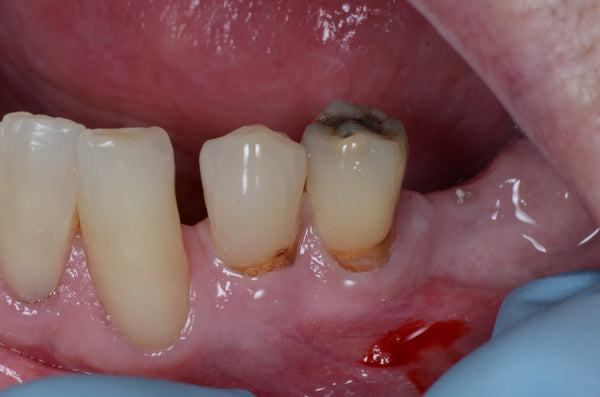

Greater Curve Band and Stamp Technique

Introduction: This case was completed by Dr. Sunny in the UK. He offers one day courses in the UK covering the Greater Curve technique. https://drecomposite.com/ This is a great challenging... Read More